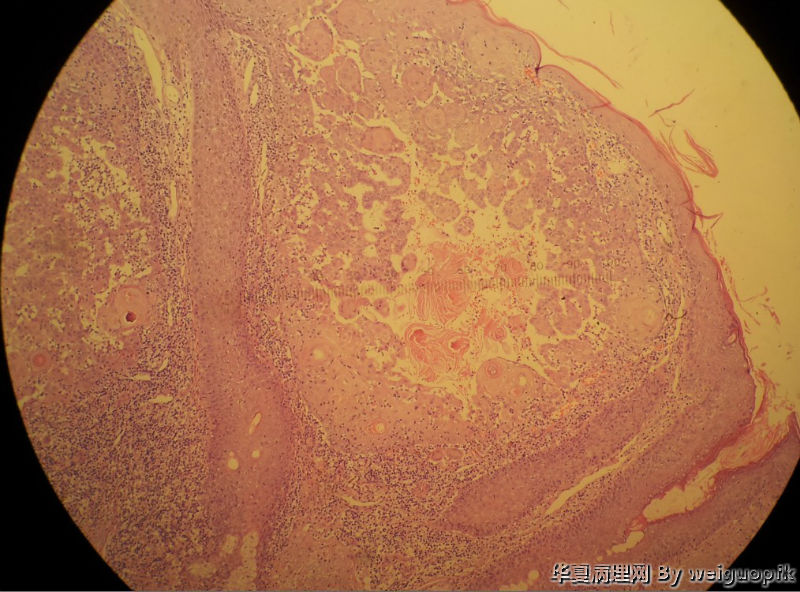

男性患者,52岁。鼻根部增生物3月余,无自觉症状。

自述3月前鼻根部出现一黑褐色丘疹,自行抠掉后,很快又有新生物长出,并逐渐增大。

患者全切后病理

另一切面

我的最终诊断是,激惹型脂溢性角化病并囊肿破裂继发异物反应。